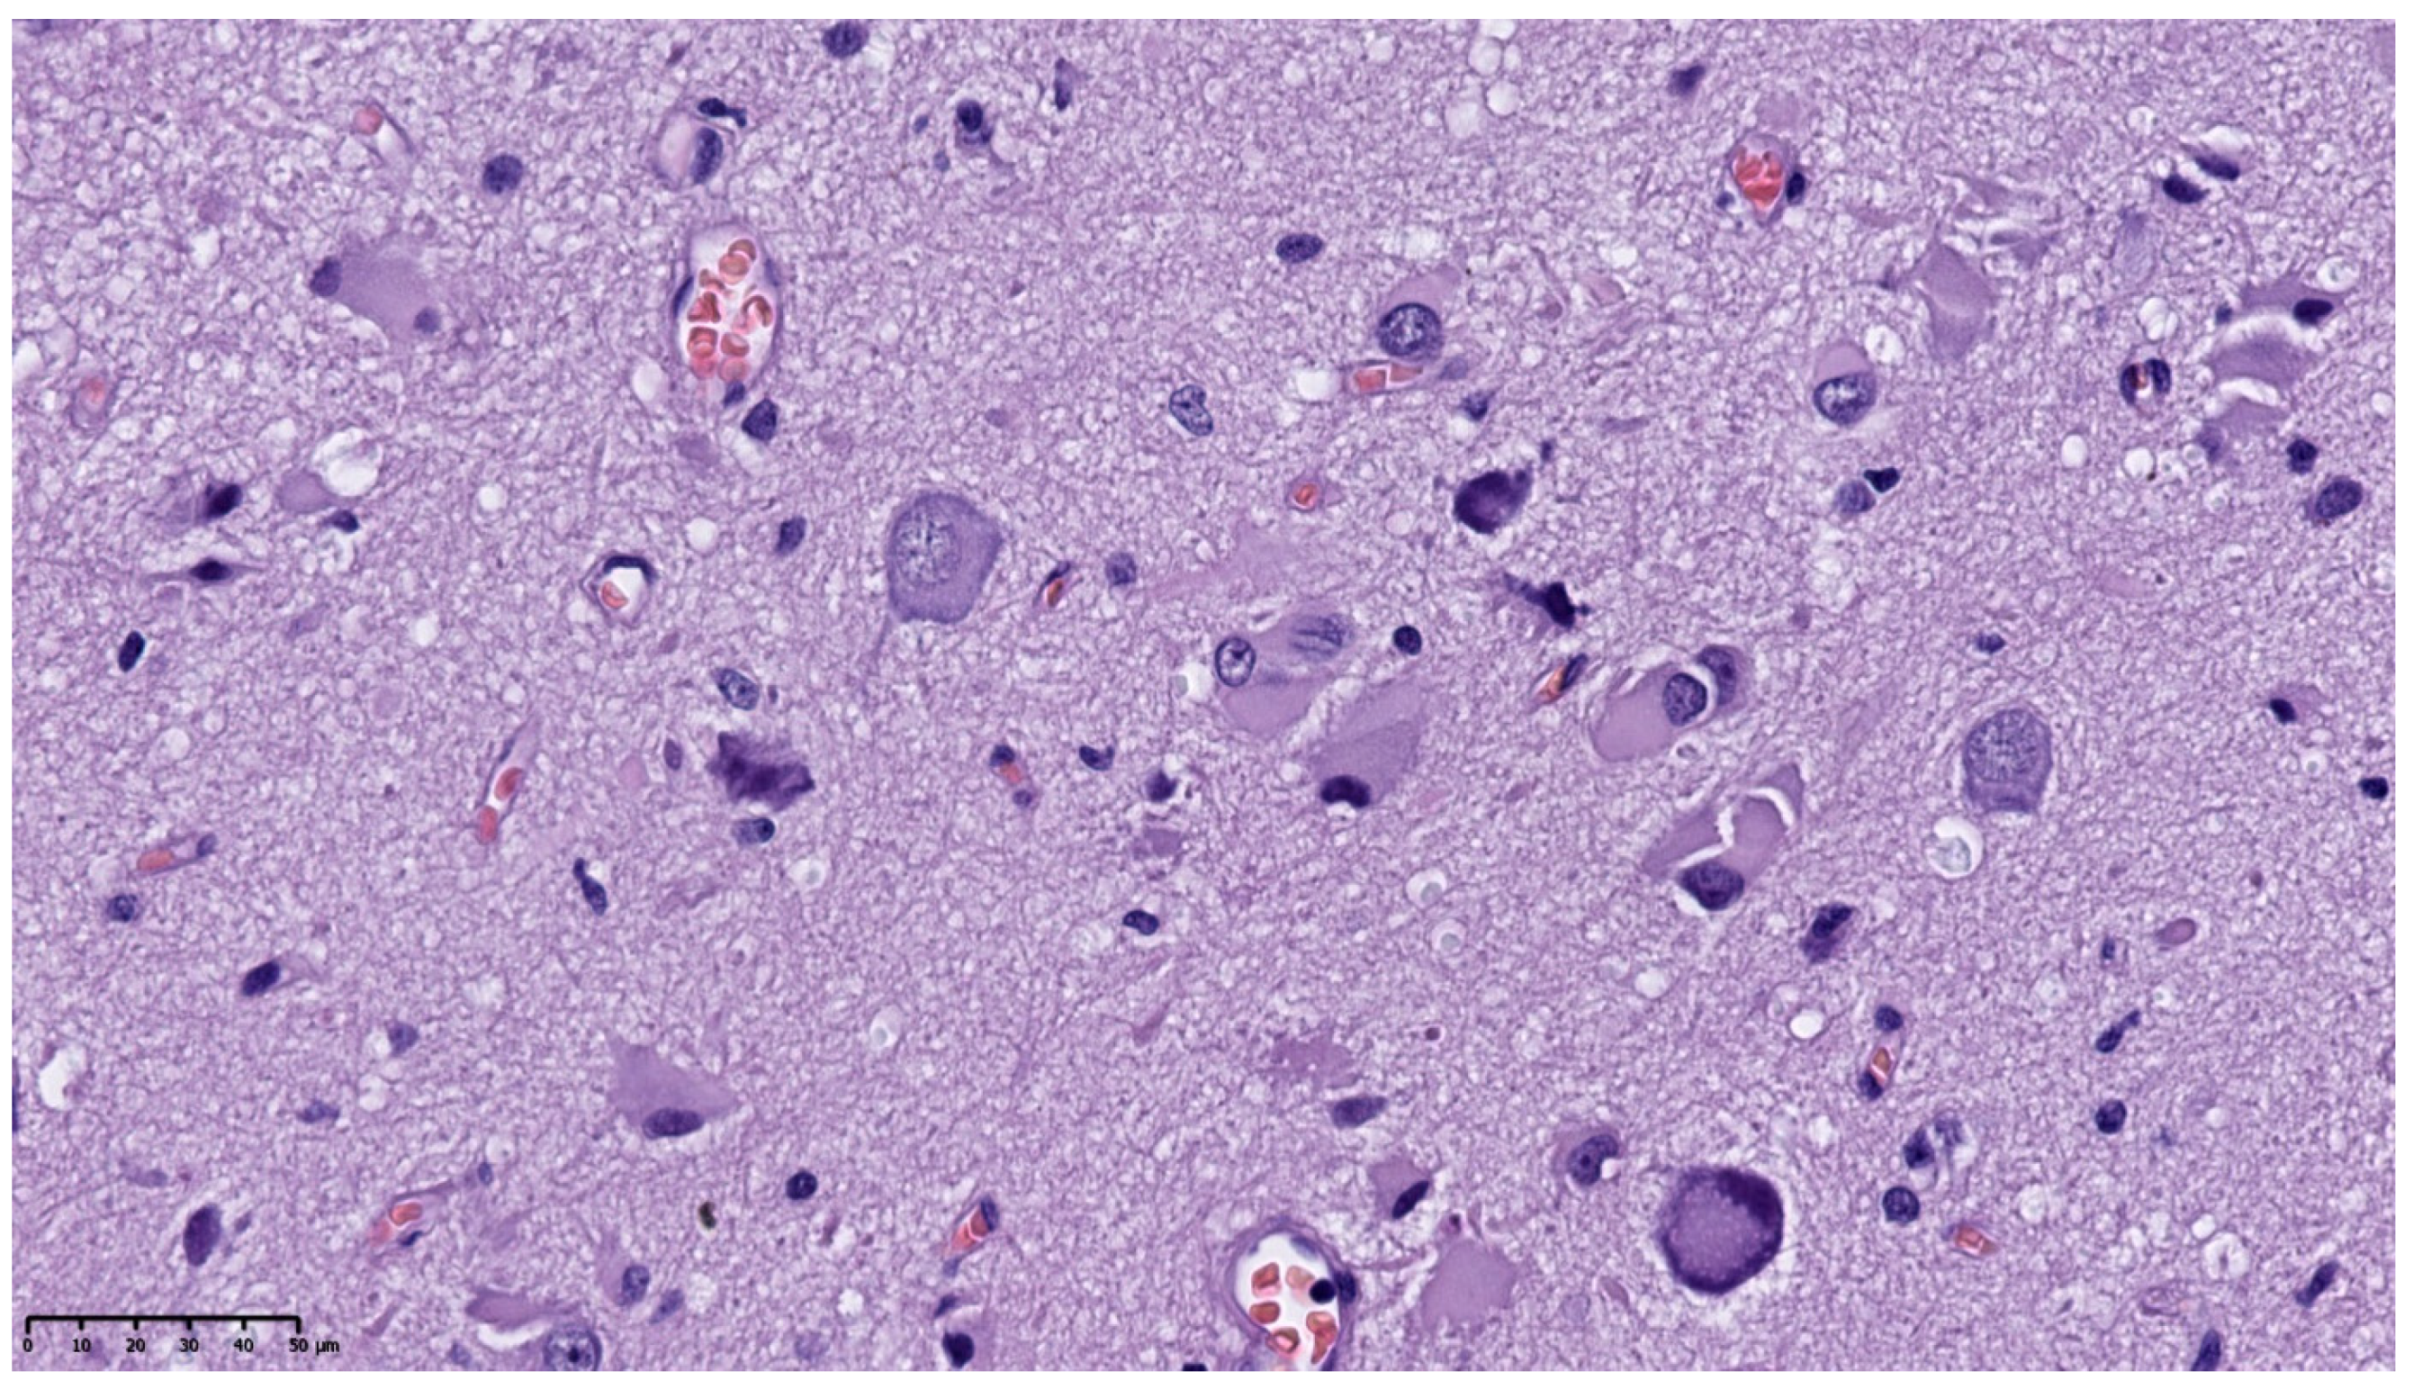

Histopathological analysis of the brain tissue obtained from the temporal lobe of the enlarged left hemisphere revealed a widened, abnormal cortex ribbon without demarcation from subcortical white matter. The complete loss of horizontal cortical lamination was observed (Figure 2).

Hematoxylin and eosin staining (HE). Disorganized cytoarchitecture of cerebral cortex (100×).